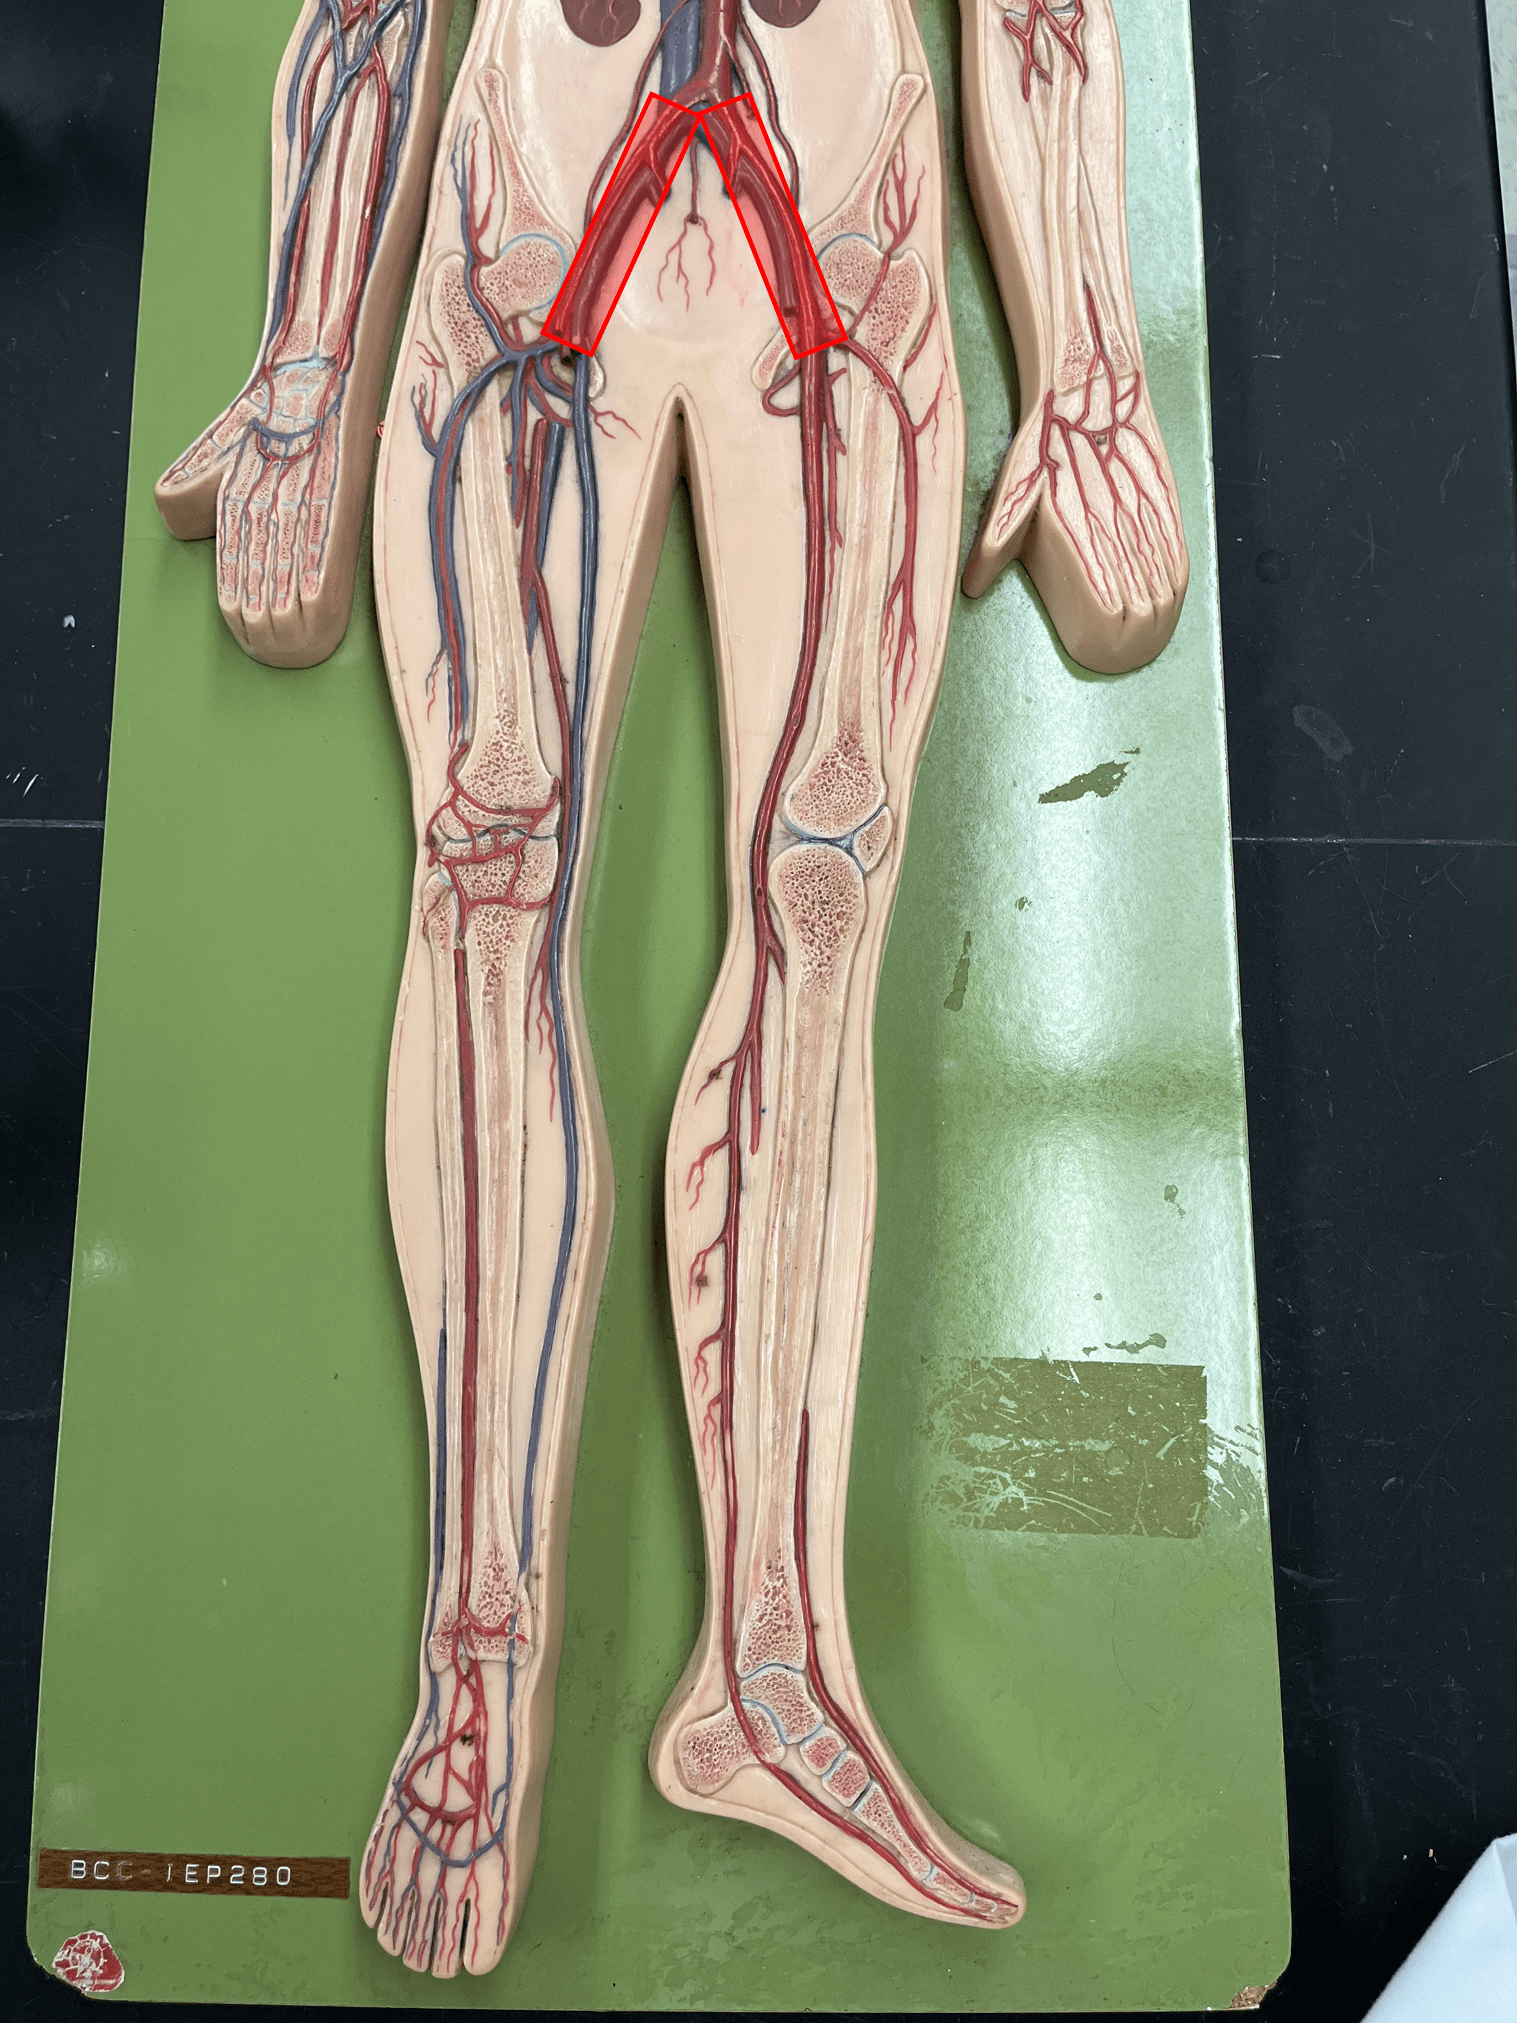

11

New cards

endothelium